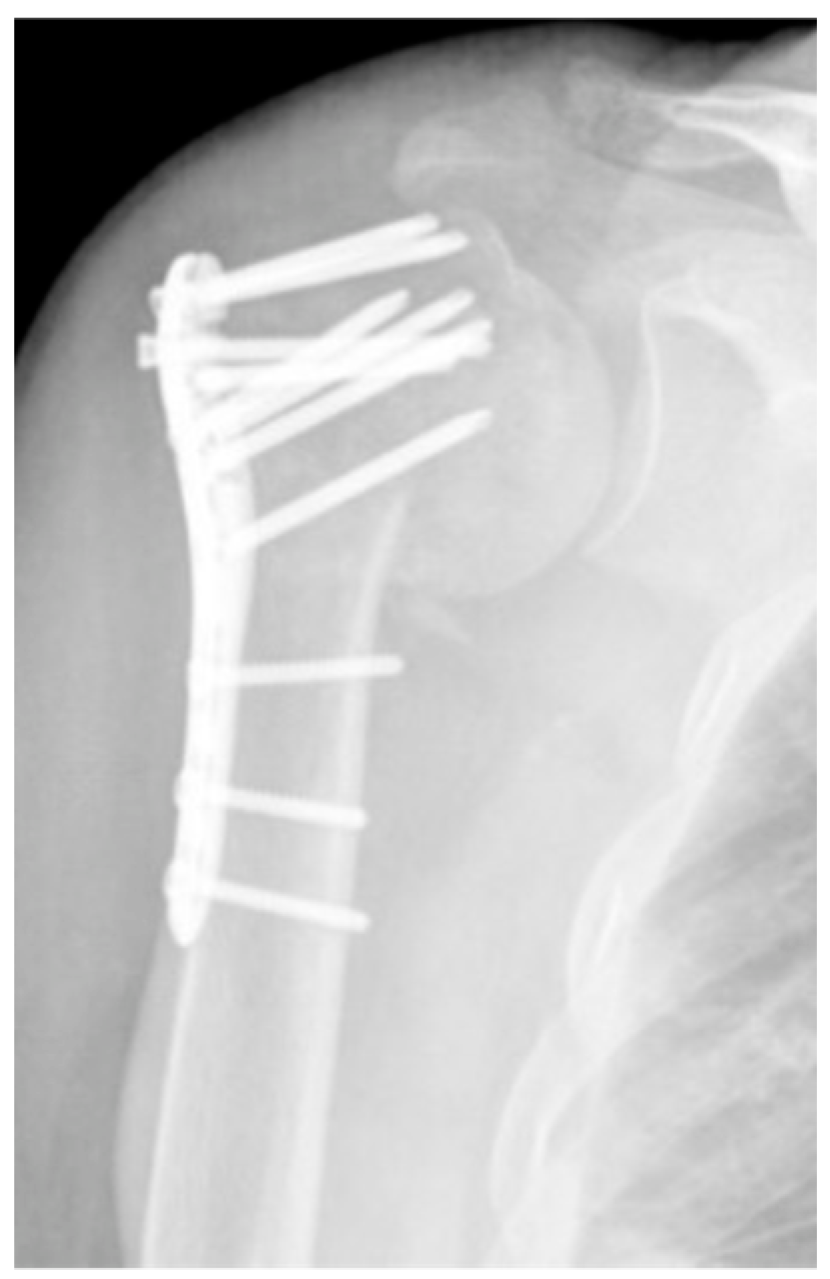

| Complication Type | Exemplary Images by X-rays or Pattern Images | Definition |

|---|---|---|

| 2a | ![]() | Complication Type 2a is defined by varus displacement (<20°) of the humeral head associated with screw cutout through the humeral head cortex. The head sintering is considered relatively stable and non-progressive. |